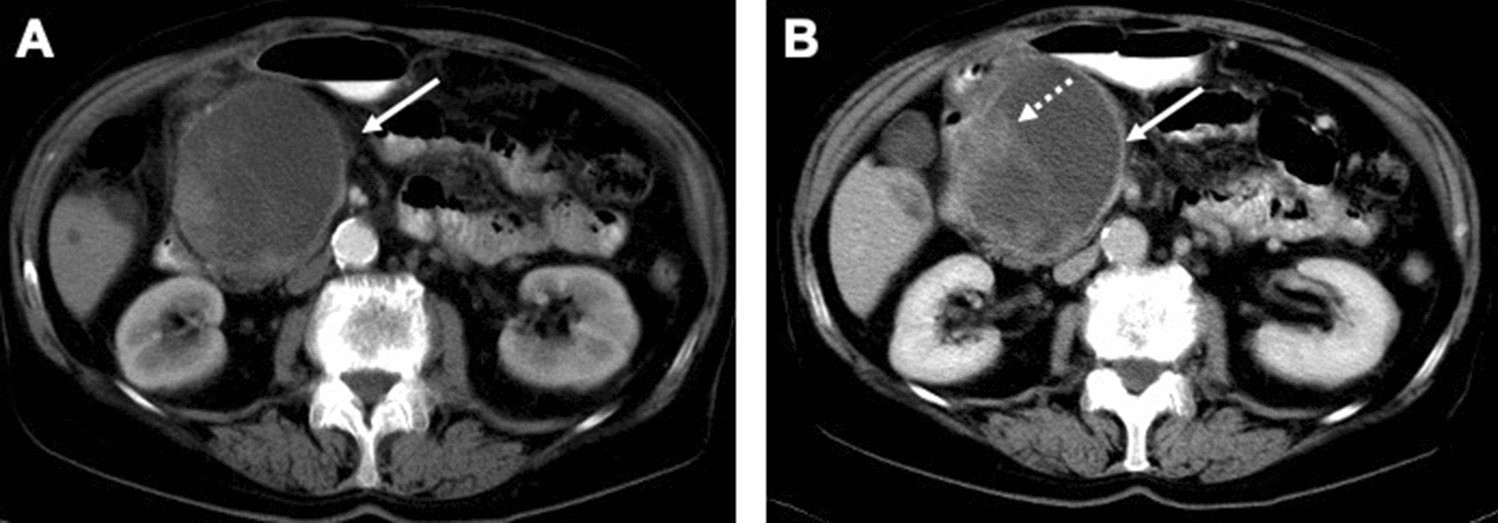

Figure 4

ITPN mimicking the morphology of mucinous cystic neoplasm. (A,B) Axial CT scans in the arterial phase (A) and portal venous phase (B) demonstration a huge oligocystic mass (arrow) in the pancreatic head with an enhancing solid nodular component (dotted arrow).